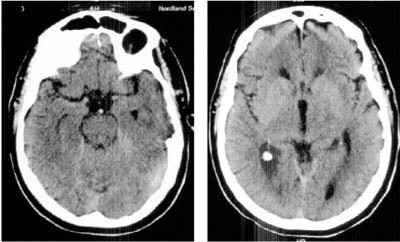

Artikkel

Ny cerebral CT ca. 25 timer etter hendelsen viste utbredt infarsering av hjernestamme, cerebellum og begge oksipitallapper samt begynnende hydrocephalus (fig 3). Gransking av arkografiundersøkelsen viste ingen fylling av venstre a. vertebralis og bare en meget langsom fylling av sentrale deler av en tynn høyre a. vertebralis. Det var ingen kontrastfylling av a. basilaris (fig 2).